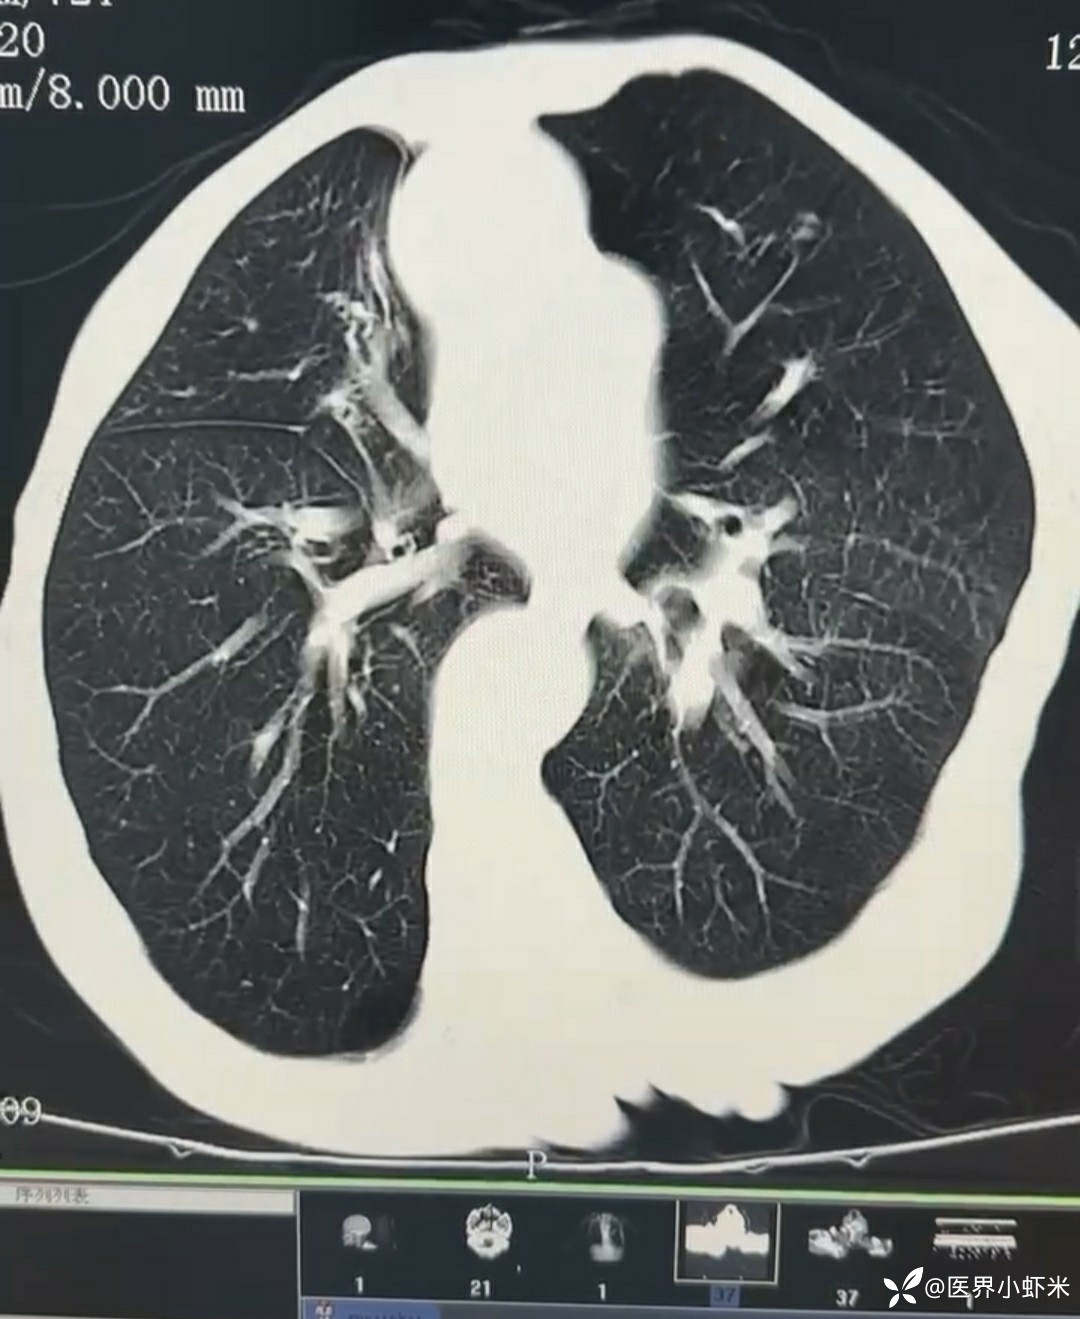

目前考虑:1.中央型肺癌伴2.肝继发恶性肿瘤?2.左丘脑继发恶性肿瘤?3.左丘脑出血?4.肾功能不全5.肝功能异常6右肾萎缩7.肺部感染8.慢性阻塞性肺病7.高血压3级(极高危)。